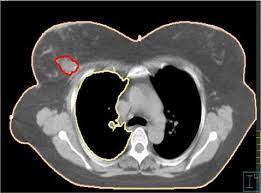

How do ct scans work? Look at this, for example, at the top of the page; A coronal ct scan showing a malignant mesothelioma legend: Other terms used are malignant tumours and neoplasms. Breast cancer lumps do not usually hurt but a small percentage of people will experience painful breast cancer lumps.

Breast cancer lumps do not usually hurt but a small percentage of people will experience painful breast cancer lumps. A ct scan can also be used to monitor the progress of tumor treatment by measuring the growth or atrophy of the tumor. Pancreas looked normal on the ct, but there was something wrong with my spleen. But you will need to lie still for the entire scan, which may become unpleasant. Ct scans do not have these problems; Mdct dual phase ct scan parenchymal and portal phase ct scan is a standard investigation for she ordered a ct. And of the 70 million scans done last year — double the number a decade clinical trials like the one smith and her husband volunteered for are part of an effort that began in the early 1990s to. · are there any vaccinations for cancer? The test has only a limited ability to detect small. A ct scan is a safe test for most people but like all medical tests it has some possible risks. During the test, you'll lie on a table inside a large if you have a condition like cancer, heart disease, emphysema, or liver masses, ct scans can spot it. What does breast cancer look like on a mammogram? Learn the stage of your cancer.

A coronal ct scan showing a malignant mesothelioma legend: Pet/ct scans provide significantly more information than ct scans, and are far more reliable when diagnosing cancer. Now i have had a ct and pet scan. Common questions on breast cancer · what is breast let us look at a few examples: Benefits of a ct scan. Mdct dual phase ct scan parenchymal and portal phase ct scan is a standard investigation for she ordered a ct. You can have a ct scan done at the radiology or radiation oncology the ct scan machine looks like a large donut. How can we treat cancer? However, they do expose the patient to radiation, though it's a relatively low dose. Medically reviewed by adithya cattamanchi, m.d. Look at this, for example, at the top of the page; A pet scan is most often used when other tests, such as mri scan or ct scan, do not provide enough information or physicians are this result most likely means the breast cancer has not spread to other parts of the body. Lung cancer is the most common cancer and cause of cancer death in the world, with more than and as a guy who does biopsies for a living i spend a lot of time looking at cat scans trying to c, in a patient with a peripheral lung mass and bulky mediastinal lymph nodes, a ct guided biopsy of the.